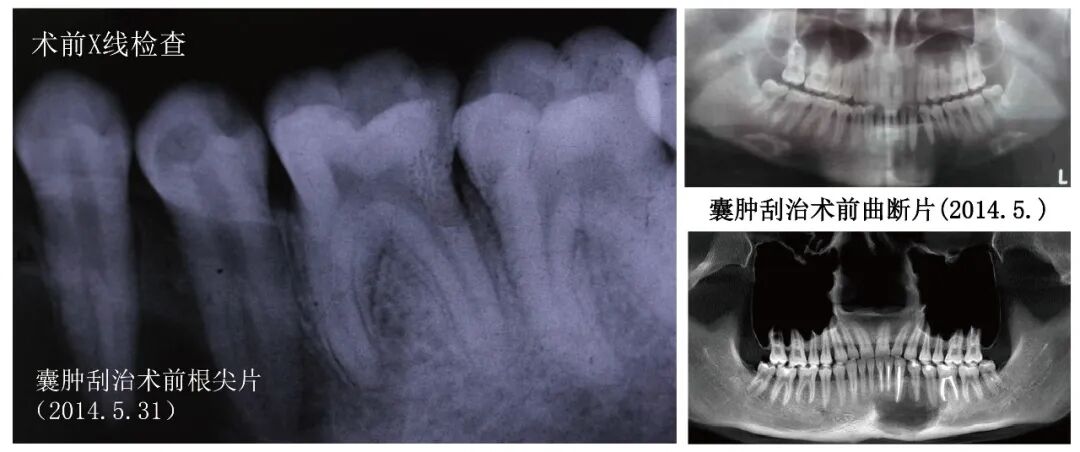

Auxiliary Examination: Pre-operative periapical radiographs indicate that the main canals of teeth 34 and 35 split into two smaller canals in the middle segment of the root, with a visible longitudinal root surface groove in tooth 35. Post-operative CBCT after cyst curettage shows dense filling material in the canals of teeth 31, 32, 33, and 36; no filling material is seen in the canals of teeth 34 and 35, and the cross-section of the roots and canals is C-shaped.

Pre-operativeX-ray examination

Post-curettage, pre-treatment CBCT for teeth 34 and 35 (2014.8.12)